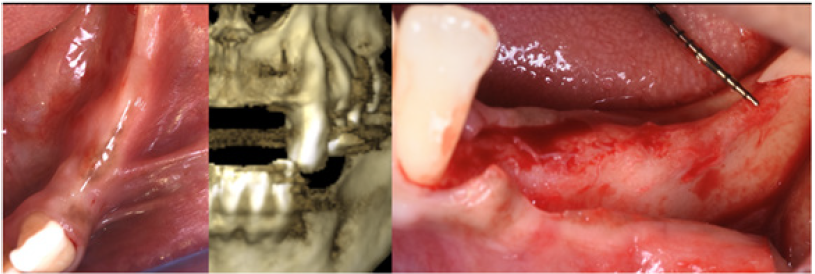

A male patient 40 years old, affected by periodontitis grade IV referred to the clinic looking for a solution for his edentulous ridges. The CBCT showed a severely resorbed ridge at some points only one mm thick. Patient was in good health and accepted to undertake GBR in all edentulous areas by mean of the F.I.R.S.T. technique. The indication in this specific case was justified by the severe horizontal resorption, using some kind of ‘sticky bone’ would enhance the chances to obtain stability of the graft and good support for the cortical lamina placed on top of the augmented area. After local anesthesia with Articaine 1.200.000 full thickness buccal and lingual flaps were elevated to display what was already known from the CBCT (Figure 16). With a piezo surgical device, the buccal cortical bone was perforated in several different points to

The protocol used to hydrate the cortico cancellous porcine xenograft (GenOs Osteobiol, Tecnoss, Coazze, Italy) was the same previously described, the use of the FS eases the stability and stickiness of the graft that adheres well to the edentulous ridge now measuring 5mm in width. The addition of the cortical lamina glued by means of FS to a well set bone graft further increases the size of the ridge (Figure 18). In this specific case was important to over-contour the regeneration anticipating some kind of remodeling due to the fact that the patient was using a removable partial denture. Because of his edentulism it was not possible to restrain the patient from the use of his denture, for this reason the augmentation provided an overcorrection of the defect anticipating some kind of remodeling with the use of the denture (Figure 19). Six months later it was possible to insert 3.4mm diameter implants in the ridge that at baseline was 1 mm thick, the new ridge was now 5mm wide. The two implants were restored with a long term temporary restoration (acrylic re-inforced with Kevlar) and three years after loading everything remained stable (Figure 20-23).

The protocol used to hydrate the cortico cancellous porcine xenograft (GenOs Osteobiol, Tecnoss, Coazze, Italy) was the same previously described, the use of the FS eases the stability and stickiness of the graft that adheres well to the edentulous ridge now measuring 5mm in width. The addition of the cortical lamina glued by means of FS to a well set bone graft further increases the size of the ridge (Figure 18). In this specific case was important to overcontour the regeneration anticipating some kind of remodeling due to the fact that the patient was using a removable partial denture. Because of his edentulism it was not possible to restrain the patient from the use of his denture, for this reason the augmentation provided an overcorrection of the defect anticipating some kind of remodeling with the use of the denture (Figure 19). Six months later it was possible to insert 3.4mm diameter implants in the ridge that at baseline was 1 mm thick, the new ridge was now 5mm wide. The two implants were restored with a long term temporary restoration (acrylic re-inforced with Kevlar) and three years after loading everything remained stable (Figure 20-23).

Figure 21: Standard diameter 3.4 mm implants placed six months after augmentation.

Figure 22: Three year follow up shows perfect stability of the regenerated bone aftyer loading.

Figure 23: Clinical view of the long term acrylic restoration.